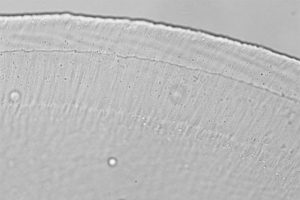

Mehr erfahren zu: "Wie künstliches Hören durch optische Stimulation natürlicher werden könnte" Wie künstliches Hören durch optische Stimulation natürlicher werden könnte Eine verbesserte Frequenzauflösung des künstlichen Hörens durch optische Stimulation des Innenohrs konnten Forscher der Universitätsmedizin Göttingen (UMG) und des Deutschen Primatenzentrums – Leibniz-Institut für Primatenforschung (DPZ) zeigen.